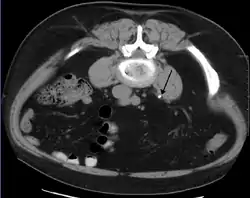

Otherwise a noncontrast helical CT scan with 5 millimeters (0.2 in) sections is the diagnostic method to use to detect kidney stones and confirm the diagnosis of kidney stone disease.[13][47][51][52][7] Near all stones are detectable on CT scans with the exception of those composed of certain drug residues in the urine,[53] such as from indinavir. Calcium-containing stones are relatively radiodense, and they can often be detected by a traditional radiograph of the abdomen that includes the kidneys, ureters, and bladder (KUB film).[53] Some 60% of all renal stones are radiopaque.[51][54] In general, calcium phosphate stones have the greatest density, followed by calcium oxalate and magnesium ammonium phosphate stones. Cystine calculi are only faintly radiodense, while uric acid stones are usually entirely radiolucent.[55]

- Bilateral kidney stones can be seen on this KUB radiograph. There are phleboliths in the pelvis, which can be misinterpreted as bladder stones.